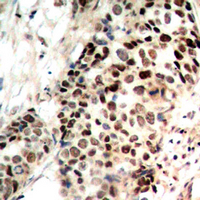

IHC (Immunohiostchemistry)

(Dilution: WB: (1/500 - 1/1000), IH (1/100 - 1/200), IF/IC (1/100 - 1/500)Immunohistochemical analysis of Histone Deacetylase 3 (pS424) staining in human breast cancer formalin fixed paraffin embedded tissue section. The section was pre-treated using heat mediated antigen retrieval with sodium citrate buffer (pH 6.0). The section was then incubated with the antibody at room temperature and detected using an HRP conjugated compact polymer system. DAB was used as the chromogen. The section was then counterstained with haematoxylin and mounted with DPX.)